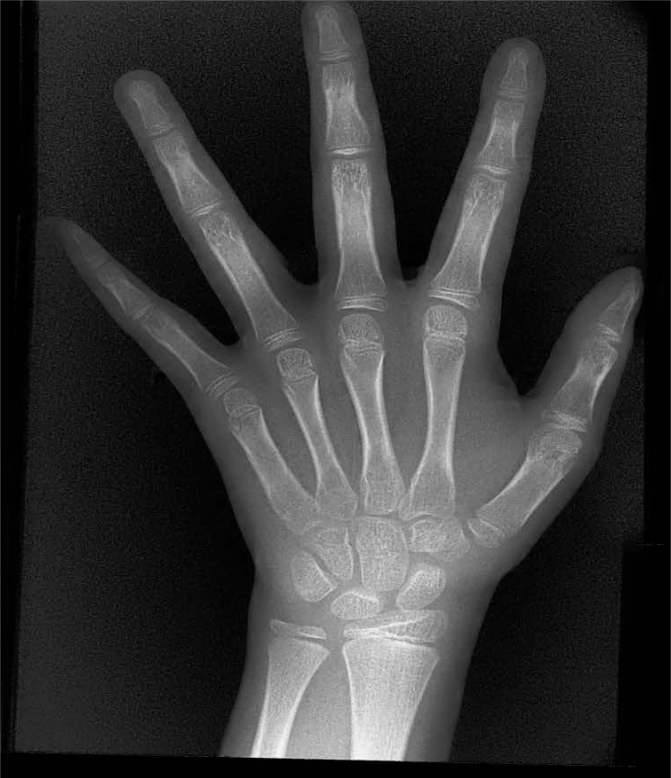

X射线骨龄仪通过拍摄儿童手腕部(指骨、掌骨、腕骨)的X射线影像,依据骨骼的形态、大小、钙化程度等特征,结合评估标准(如《中国青少年儿童手腕骨成熟度及评价方法》,简称《中华-05》标准)进行骨龄判定。相较于传统检测方式,X射线骨龄仪具有辐射剂量低、影像清晰度高、检测效率高的优势,能精准捕捉骨骼发育的细微变化,为骨龄评估的准确性提供保障。